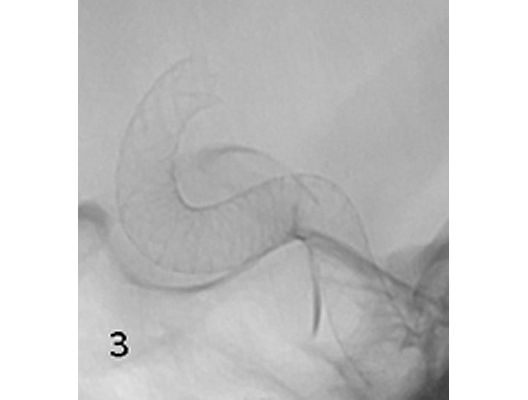

Mit den modernen Verfahren zur Wiedereröffnung von verschlossenen Blutgefäßen können wir Patienten mit Schlaganfall in vielen Fällen helfen. Das folgende Beispiel zeigt die angiographischen Bilder eines Patienten, der mit vollständiger Lähmung der rechten Körperhälfte und einer schweren Sprachstörung eingeliefert wurde. Ursächlich zeigte sich ein Verschluss der linken Halsschlagader, vermutlich auf dem Boden einer arteriosklerotischen Einengung (Bild 1). Das Gefäß wurde daraufhin mit einem Stent wiedereröffnet (Bild 2). Zusätzlich zeigte sich ein Verschluss der Endstrecke des Gefäßes durch Blutgerinnsel (Bild 3). Diese konnten vollständig entfernt werden (Bild 4). Der Patient erholte sich nach der Behandlung innerhalb weniger Tage vollständig.

Das Beispiel zeigt die angiographischen Bilder einer Patientin, bei der es zu einer Sehstörung gekommen war. Die Ursache war ein großes Aneurysma der Halsschlagader an der Schädelbasis (Bild 1). Bild 2 zeigt die Lage des Aneurysmas hinter dem Auge. Durch den Druck des Aneurysmas auf den Sehnerv war es zu der Sehstörung gekommen. Die Patientin wurde mit einer speziellen Gefäßprothese versorgt, welche über eine Punktion der Leistenarterie in die Halsschlagader eingesetzt wurde (Bild 3). Bei der Kontrolle nach 6 Monaten zeigte sich ein vollständiger Verschluss des Aneurysmas (Bild 4). Die Sehstörung hatte sich vollständig zurückgebildet.